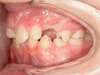

Cas 4 : Description

Chevauchement sévère. Traitement multibague sans extraction.

Avant

Après